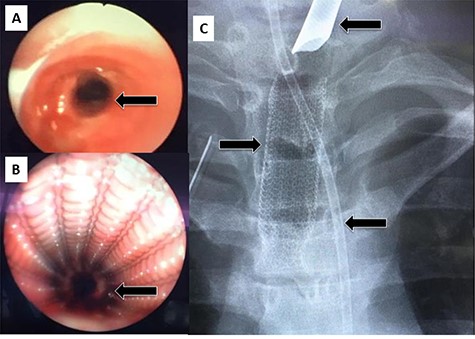

After 1 month, the patient again presented to the ED with stridor and respiratory distress and was shifted to the OT. Bronchoscopy revealed granulation tissue obstructing the distal tracheal margin. A 7.5 sized ETT was passed through the stenotic site, with a plan for removal of the granulation tissue and replacement with a new (longer) stent. Rigid bronchoscopy revealed the lower end of the stent to be embedded in granulation tissue. Blunt dissection was performed to free up and removal of the stent (Fig. 5A and B). However, immediately after stent removal, the patient developed severe hypoxia, hypotension and bradycardia. The cervical trachea was opened longitudinally, and attempts were made to pass the ETT tube ‘manually’ across the stenosis, which also failed. At this point, the patient went into cardiac arrest, and CPR was started. A right anterolateral thoracotomy and lower sternotomy were performed, with open cardiac massage. The mediastinal trachea was exposed and opened anteriorly/inferiorly, and two small ETT’s were placed into each main bronchus. Attempts to establish an opened airway distal to the stenosis and to resect it was not successful as the patient condition quickly and progressively deteriorated. Unfortunately, despite resuscitative efforts, the patient was declared dead.

(A) Rigid bronchoscopy revealed the lower end of the stent to be embedded in granulation tissue. (B) The stent after removal showing the distal part with granulation tissue.